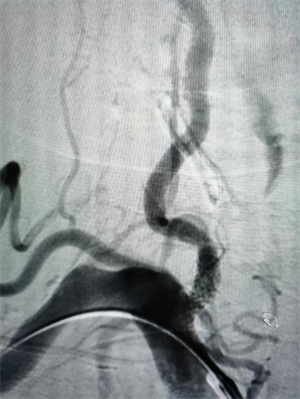

△图一:手术前可见后交通动脉瘤合并多个突起

△图二:手术后动脉瘤已经栓塞,造影不可见